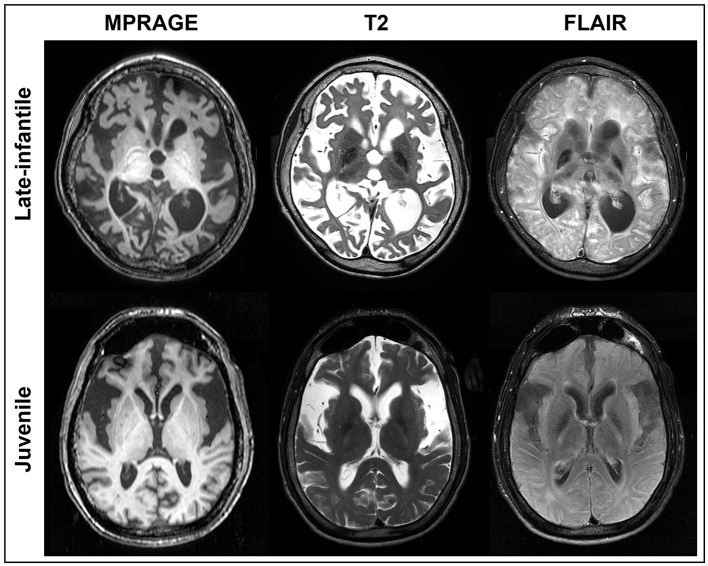

Approach: Twenty-five brain MRIs were included in this study from 22 type II GM1 patients of which 8 were late-infantile subtype and 14 were juvenile subtype. The following structures were segmented by two rating teams on a slice-by-slice basis: whole brain, ventricles, cerebellum, lentiform nucleus, thalamus, corpus callosum, and caudate nucleus. The inter- and intra-rater reliability of the segmentation method was assessed with an intraclass correlation coefficient as well as Sorensen-Dice and Jaccard coefficients.